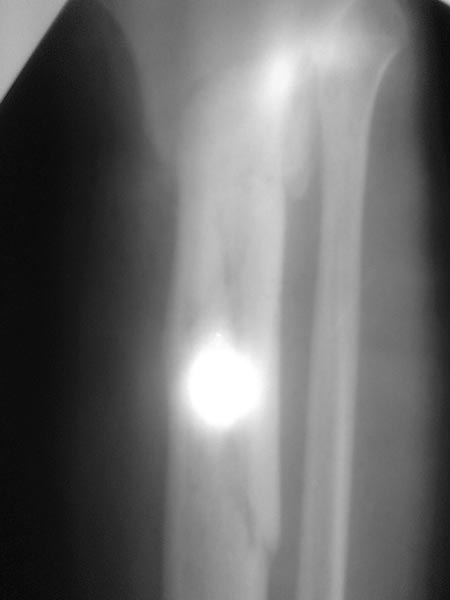

Все таки решились на штифт с антибиотическим покрытием. Выставляю R, в целом считаю неплохо вроде получилось.

Спасибо за обсуждение.Отправил остальные R, изиняюсь за качество.